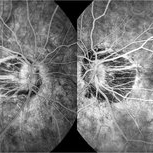

Fluorescein Angiography in High Myopia

Dec 7 2019 by Anfisa Ayalon, MD

Fluorescein angiography pictures of a 55-year-old woman with high myopia.

Photographer: Anfisa Ayalon, MD., Meir Medical Center, Kfar Saba, Israel.

Condition/keywords: fluorescein angiogram (FA), high myopia, peripapillary atrophy